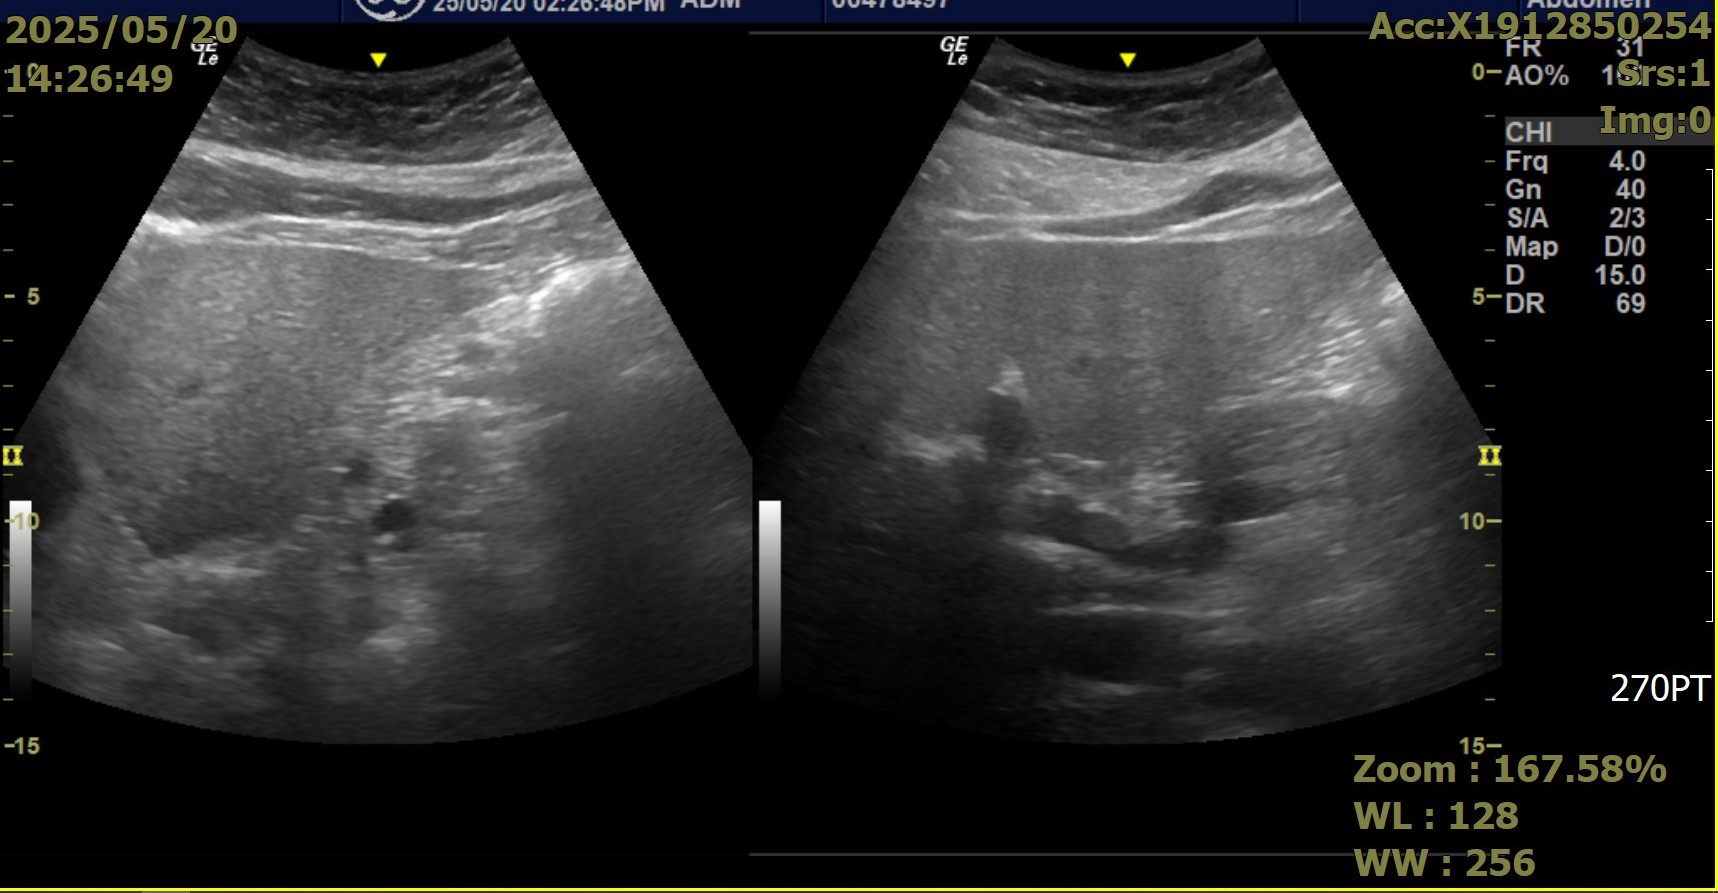

圖:新營醫院正與台南第二監獄(南二監)聯手打一場漂亮的「肝臟保衛戰」!(新營醫院提供)

一名陳姓收容人就是最佳見證。今年初篩檢時,他的C肝病毒量高達79,000 IU/mL,情況嚴峻。自3月5日起,他接受為期兩個月的口服抗病毒藥物治療。奇蹟發生了——5月初的追蹤檢查顯示,病毒量已「測不到」!儘管初戰告捷,醫療團隊仍嚴謹以待,將持續進行12週追蹤,確保病毒徹底「清零」,杜絕復發可能。這個案例完美體現了「診斷即治療」政策的威力!